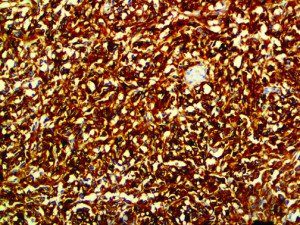

The first cytokines released are interleukin 1β (IL-1β) and tumor necrosis factor-α (TNF-α), which attract a variety of circulating white blood cells (WBCs) to the infection site, including neutrophils, monocytes, macrophages, and natural killer (NK) cells. This response, along with the antipathogenic chemicals released by these cells (i.e., complement), comprise the innate immune response. These cells directly attack the invading pathogen and also release additional cytokines, chief among them interleukin-1 and 6 (IL-6). IL-6 is essential for invoking the adaptive immune response, which calls T-cells, B-cells, and T helper (Th) cells to the infection site. IL-6 also stimulates further recruitment, proliferation and activation of macrophages.

It is the ICU physician who is most likely to witness one of the deadliest manifestations of the abnormal immunological response, the cytokine storm syndrome (CSS). This response is also referred to by some as the cytokine release syndrome (CRS). CSS is characterized by continuous activation and expansion of macrophage and lymphocyte populations, which secrete large amounts of cytokines, causing the cytokine storm. This massive cytokine release is akin to hemophagocytic lymphohistiocytosis (HLH) disease, a syndrome characterized by initial unchecked and persistent activation of cytotoxic T lymphocytes and NK cells.

This activation induces inflammatory monocytes to highly express IL-6, starting a localized and then systemic cascade effect that results in hyperproduction of IL-6, which accelerates the inflammatory process. Because IL-6 also increases vascular permeability, excessive levels cause blood vessels to become very leaky. This, along with clotting factors released from vascular endothelial cells, stimulates the coagulation cascade, resulting in microthrombosis (tiny clots), which leads to ischemia and tissue death of the kidney, intestines, heart, liver, brain and extremities.